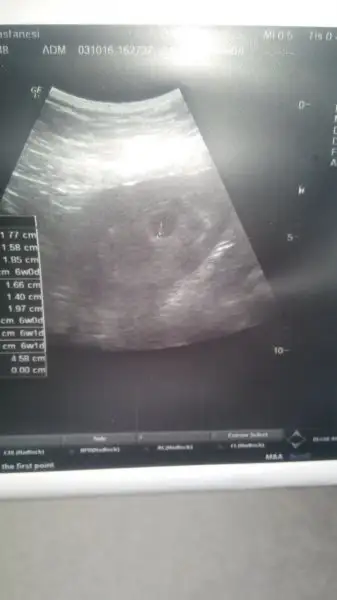

Kiz bence canim :)Merhaba kizlar .. Benimkine de bakar misiniz 8+6 yiz :)Havalianne__

Merhaba kizlar .. Benimkine de bakar misiniz 8+6 yiz :)Havalianne__